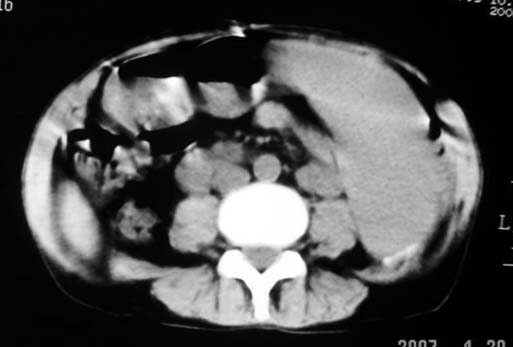

以下是引用dyqct在2007-4-20 16:38:00的发言:[br]考虑:1、巨脾;[br] 2、肝内多发低密度,首先考虑转移瘤;[br] 3、胆囊多发结石。

以下是引用andymaomao在2007-4-20 16:47:00的发言:[br]肝脾增大,肝内胆管扩张,且可见多发小囊性低密度灶,胆囊窝区高密度影,手术化疗病史,贫血....[br]1.肝脾大及贫血与术后化、药疗有关;[br]2.胆囊窝区高密度影,术后改变?肝内胆管扩张,积液?[br]3.肝内多发低密度灶,性质?建交增强